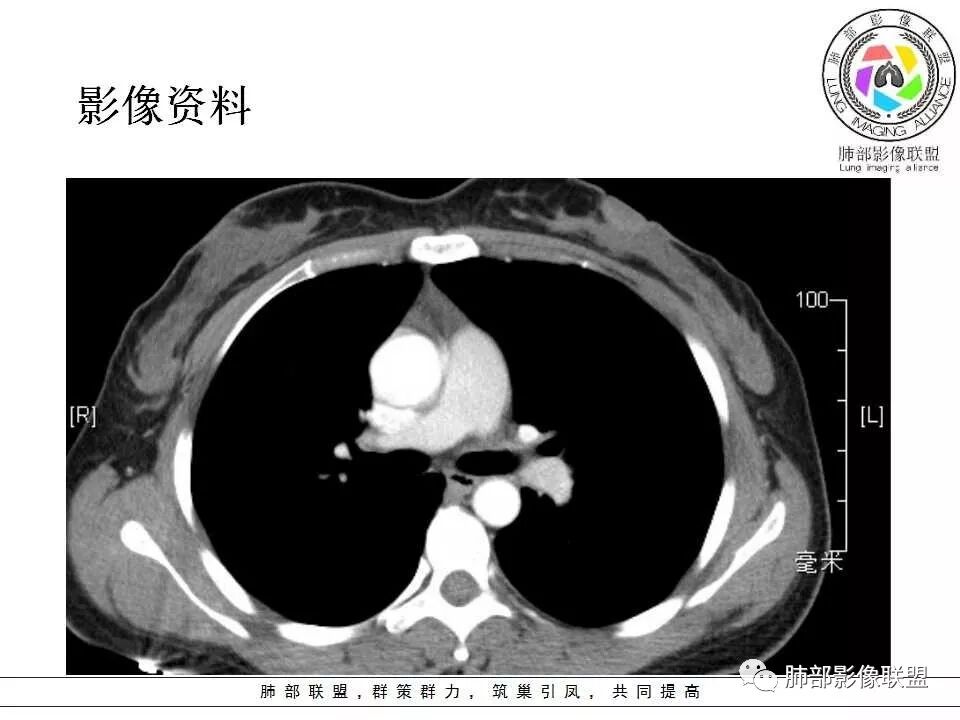

左肺门肿块,边缘光滑清晰,血管贴边,明显均匀强化,考虑PSP,鉴别类癌。

学习一下南大的诊断思路,左肺门区病灶,应该没跨叶,感觉都在上叶,强化密度均匀,边缘清晰,与支气管关系不大,常规考虑良性病变,PSP可能性大,鉴别CD,血管源性。但是一年增大怎么解释,不知道增大多少。

左肺病灶与支气管关系密切,类癌粘膜下生长,支气管略变窄,支气管外病变较大,符合冰山征表现,一年内有增长,考虑类癌,鉴别PSP,建议薄层重建。

我怎么又感觉跨叶间裂了,而且有胸膜尾征和可疑的指状突起,强化很明显,考虑SFT可能大,鉴别类癌和CD

年轻女性,左肺门区肿块,边缘光整,随诊有增大,恶性可能,类癌?鉴别psp、CD。

患者中年女性,发现左肺上叶占位,随访发现体积增大。胸部CT:左肺上叶尖后段实性占位,位于支气管旁,未见支气管阻塞,病灶边界清楚,边缘光滑,增强可见病灶均匀强化,血管贴边,考虑良性病变,PSP?

左肺上叶后段紧贴斜裂结节影,支气管通畅,斜裂无移位,说明病灶来源斜裂可能,强化密度均匀,边缘清晰,考虑良性病变,PSP可能性大,鉴别CD。

青年女性,慢性病程,实验室指标末提及,左肺门区肿块,边缘光滑,无明显分叶,周围清晰,增强明显强化,血管贴边,复查有增大,考虑良性或低度恶性病变,PSP?

患者中年女性,发现左肺上叶占位1年余入院,随访发现体积增大。胸部CT:左肺上叶尖后段近肺门及叶间裂实性类圆形结节,病灶边界清楚光滑,增强可见病灶明显均匀强化,其旁未见支气管堵塞。综合考虑良性病变,孤立性纤维瘤可能,鉴别巨大淋巴结增生症及硬化性肺细胞瘤。

青年女性,左肺门占位,边缘光滑,强化均匀,考虑为良性病变,PSP可能,近期复查增大,不除外恶性病变。

年轻女性,体检发现,左肺上叶近肺门处结节,边缘光滑,均匀明显强化,血管贴边,支气管无关,考虑PSP。

中年女性,发现左肺上叶占位。胸部CT:左肺上叶尖后段孤立卵圆形实性病灶,位于支气管旁,边界清楚,边缘光滑,血管贴边,肺动脉为主征,增强扫描明显均匀强化。考虑:PSP?鉴别CD、类Ca。

青年女性,左肺门占位。定位:跨叶间裂,下叶邻近支气管推压,考虑肺外病变。影像表现:血管贴边,边缘光滑,强化均匀,考虑良性病变,PSP可能大,鉴别CD。

左肺上叶类圆形实性病灶,边缘光滑,可见血管贴边征,病灶与左肺上叶支气管关系密切,左肺动脉相对增粗,增强病灶均匀强化,常规考虑PSP,其次神经内分泌肿瘤不排除。

厚层,只有动脉期。左肺门占位,边界清,动脉期强化比较明显,后段支气管不明确,考虑恶性,类癌可能。psp渐进性强化,动脉期好像没这么明显。

年轻女性,左肺门肿块,边缘光滑,密度较均匀,增强后肿块明显均匀强化,血供丰富,病史提示一年明显增大,也说明富血供,常规考虑PSP,类癌待排。

年轻女性,边缘光滑圆形肿块,均匀强化,血管贴边儿,常规考虑硬化性肺细胞瘤(PSP)。不放心的地方就是幻灯第22幅,似乎有一个小尾巴。巨淋巴结增生症(CD)及类癌待排。CD这个部位可以,但是相对少见的多。类癌的话强化可以,但是形态太规整了,似乎也不符合。潘老师还说过一个糖瘤,忘记长啥样儿了。

中年女性,查体发现,偶有咳嗽,左肺上叶近肺门肿块,边缘光滑,密度均匀,有强化,与支气管关系不清,有血管贴边,随访有增大,还是先考虑低度恶性肿瘤,类癌可能,鉴别psp。

青年女性,一年前发现肺结节,复查有增大,未见近期片对比,定位:左肺上叶左肺门旁见实性类圆形结节,边界清晰光整,有部分分叶征,增强有均匀强化,与左上叶后段支气管关系不好判断,左上叶后段支气管未显示,堵塞?狭窄?需冠矢状面看看,定性:常规考虑良性或低度恶性肿瘤,典型的类癌或硬化性肺细胞瘤psp可能,神经源性或神经内分泌肿瘤、巨淋巴结增生症CD不除外,转移瘤、孤立性纤维瘤待排,建议HRCT或支气管镜检查。

年轻女性,左肺门区占位,斜裂推移未跨叶,类圆形,增强扫描明显强化,和支气管关系显示不是太清楚,感觉关系不是太密切,未见阻塞性炎症,一年后有长大,首先考虑PSP,鉴别类癌,SFT。

左肺门区肿块,形态规则,边缘光滑,密度均匀,未见支气管截断,增强后均匀强化,血管似有贴边,年轻女性,考虑PSP,鉴别:CD,副节瘤。

36岁女性,发现左肺占位1年,时有干咳。CT:左肺门(上叶尖后段?)类圆形结节,边界清,靠前边缘似有GG0,近肺门侧与血管密切接触,似有小凸起,增强见明显均匀强化,似有条片状影往肺门侧血管钻。图片有点少,病灶与支气管的关系看不清(目前的图片与支气管不密切)。随诊结节增大,整体考虑典型类癌可能性大,鉴别硬化性肺细胞瘤。